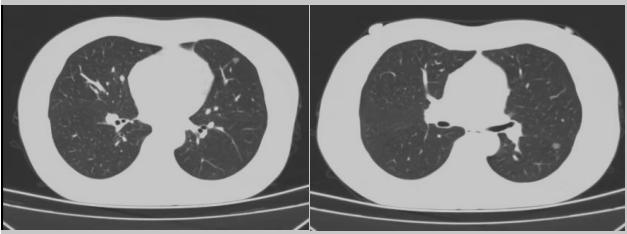

病例二:42歲的范女士,半年前體檢時發(fā)現(xiàn)雙側多發(fā)肺結節(jié),平時沒有什么不適。四個月后再次復查胸部CT,左上肺及下肺多發(fā)的磨玻璃結節(jié),其中下葉9mm的結節(jié)定為高危病灶??吹浇Y果范女士坐不住了,多方打聽慕名找到了市二院院長王瑾,經“肺結節(jié)MDT”團隊會診后,決定手術治療。入院后,胸外科副主任醫(yī)師薛飛詳細與范女士溝通,并利用Mimics做好了術前肺部三維重建手術規(guī)劃,打消了范女士心中的顧慮。經過前期充分準備后,歷經1小時30分,完成“胸腔鏡下左肺上葉舌段楔切及左肺下葉背段切除術”,術后病理檢查結果確診為左肺微浸潤性腺癌。在胸外科團隊的悉心照顧下,患者術后恢復良好,一周后順利出院。